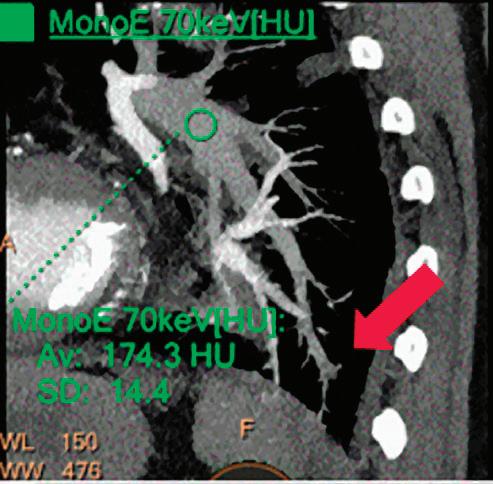

CT breath-hold results in a poor enhancement of the pulmonary arteries on the displays from left to right: monoenergetic 70 keV, monoenergetic 55 keV, monoenergetic 40 keV, and Z effective map showing a perfusion deficit of the lung parenchyma (white arrow). When decreasing the energy, the iodine attenuation is progressively boosted and reveals the presence of a thrombus (colored arrows) in a sub-segmental pulmonary artery corresponding to the territory of the perfusion deficit. (c) Monoenergetic 200 keV reduces beam hardening from dense contrast medium compared to conventional CT images.

Once the pair (αp, αc) is calculated for every voxel, and since fp(E) and fc(E) are known functions of energy, one may synthesize monochromatic images at different energies. These images can be used for routine diagnosis similar to conventional images. With a single scan at 120 kVp (or 140 kVp for obese patients), a dual-layer spectral CT acquisition allows the reconstruction of virtual monochromatic images from 40 keV up to 200 keV, in increments of 1 keV. The minimum of 40 keV was chosen in order to stay above the k-edge of the most common materials including iodine (iodine k-edge = 33 keV). If the scan is performed at 120 kVp, the conventional CT images of a typical-size patient will display an attenuation corresponding to the average of the X-ray spectrum (˜70 keV in a body scan) but with beam hardening artifacts from dense structures (like bones) which are due to the polychromatic nature of the X-ray beam. Since the photoelectric effect is dominant at lower keV, and is relatively high for high Z materials, low keV imaging (below 70 keV for body) can be used to enhance the absorption of high Z material such as iodine (Z=53), compared to the conventional CT images.15,16 This can be of particular interest to enhance the iodine uptake for patients with renal dysfunction, where the total injected volume of iodinated contrast medium is very limited. This attenuation boost can also be very useful in the case of a missed injection (Figure 2a and b). Compton scattering on the other hand is dominant at higher keVs and does not exhibit a strong relationship with Z. High keV imaging will then be of particular interest to minimize the absorption of high Z materials and minimize all types of associated artifacts (metal beam hardening from metal implants, beam hardening from dense contrast medium, blooming of stents or calcium, etc.) (Figure 2c).17,18,19

Virtual monoenergetic images obtained from the IQon Spectral CT scanner have low noise across the entire spectrum of energies,20 and this noise is lower than in conventional images due to the spectral reconstruction processing that includes noise suppression algorithms that make use of the additional spectral information. This provides significant SNR and CNR improvements compared to conventional polyenergetic images. The low noise of monoenergetic images at various energy levels makes them usable at all energy levels, particularly at low energies for enhancing vascular contrast or improving lesion conspicuity and at higher energies for decreasing artifacts.